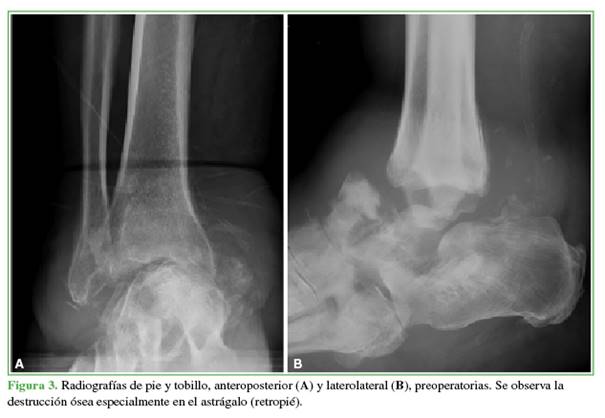

Al final del seguimiento, 7 pacientes tenían una consolidación estable de la artrodesis TTC (Figuras 3 y 4), dos desarrollaron una consolidación fibrosa que les permitió la deambulación con un equipamiento ortésico. Uno requirió una revisión tardía de la artrodesis y aún está en el período de seguimiento. La mediana de tiempo de consolidación fue de 8.6 meses (RIC25-75%: 4.7-8.6).